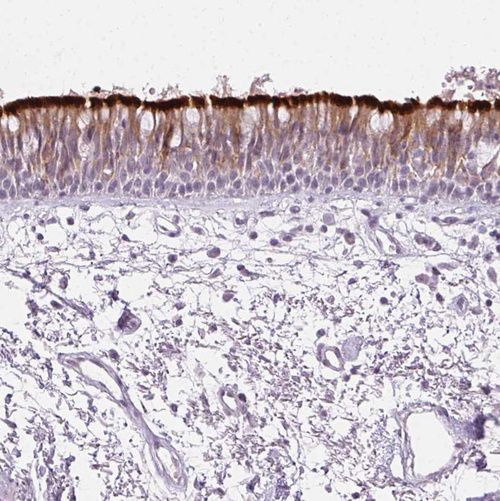

Immunohistochemistry analysis in human testis and prostate tissues using HPA041830 antibody. Corresponding ROPN1L RNA-seq data are presented for the same tissues.